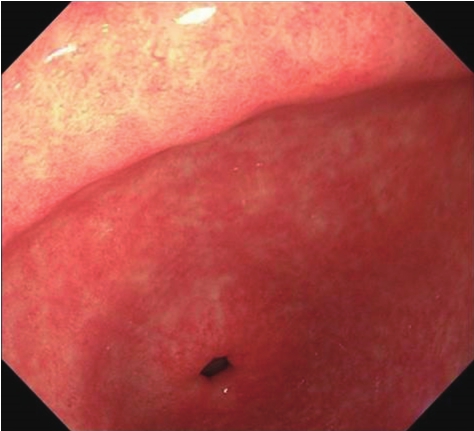

慢性萎缩性胃炎(chronic atrophic gastritis)是以胃黏膜内固有腺体萎缩减少为主要病变的一种慢性胃炎,占慢性胃炎的10%~30%,多见于中老年人,好发于幽门和胃小弯。慢性萎缩性胃炎按照病因、发病部位和临床表现分为3种类型:①A型,较少见。病变主要位于胃体部,多弥漫性分布。血清抗壁细胞抗体、抗内因子抗体阳性,血清胃泌素明显升高,胃酸和内因子分泌明显减少或缺少,维生素B 12 吸收障碍,常伴有恶性贫血,又称为自身免疫性萎缩性胃炎。②B型,较多见。病变主要位于胃窦部,呈多灶性分布,与幽门螺杆菌感染密切相关,血清抗壁细胞抗体、抗内因子抗体阴性,血清胃泌素多正常,胃酸分泌正常或轻中度减低,无恶性贫血。③C型,较多见。与胆汁反流和化学物质(乙醇、阿司匹林等非固醇类抗炎药)损伤有关。

早期黏膜红白相间或以白色为主,皱襞变细或平坦(图3-9)。严重者有散在白色斑块或呈颗粒状,黏膜变薄,黏膜下血管清晰可见,易出血,可伴有糜烂。

图3-9 慢性萎缩性胃炎

早期黏膜红白相间。